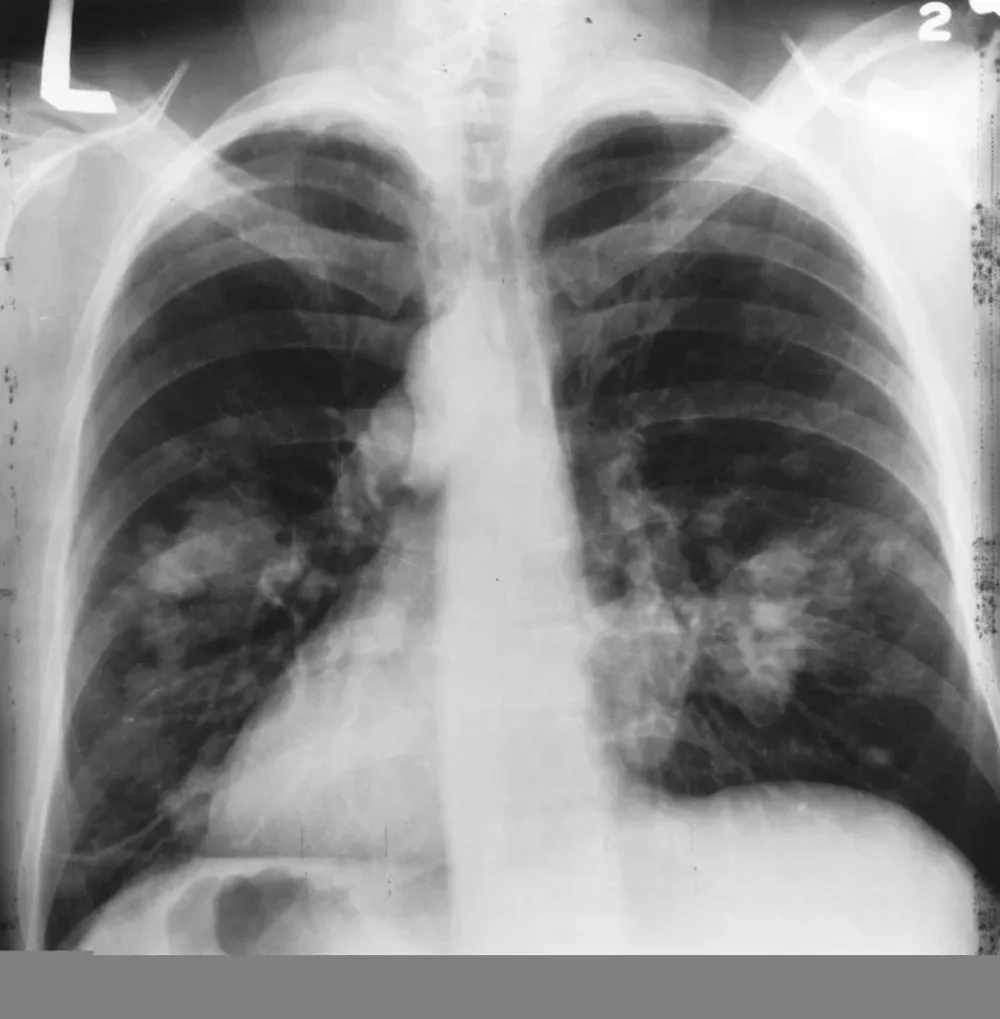

Este martes el presidente Tabaré Vázquez anunció que los médicos le habían detectado un nódulo en el pulmón derecho con características malignas. Más allá del caso del mandatario, sobre el que aún restan estudios para determinar el tipo de tumor y su tratamiento específico, ¿qué es el cáncer de pulmón? ¿Qué implica y cómo se trata?

Según el experto, lo primero que hay que hacer cuando se detecta un tumor en el pulmón es analizar las características moleculares. La detección se puede hacer a través de una radioterapia, pero siempre es necesario hacer una biopsia para conocer la entidad del tumor. Una vez que se confirma con la biopsia, lo ideal es hacer un PET, tomografía por emisión de positrones, que detecta las células cancerígenas presentes en el organismo, y una resonancia magnética a nivel cerebral. Estos dos estudios permiten detectar si la enfermedad está extendida o se trata de un tumor puntual.